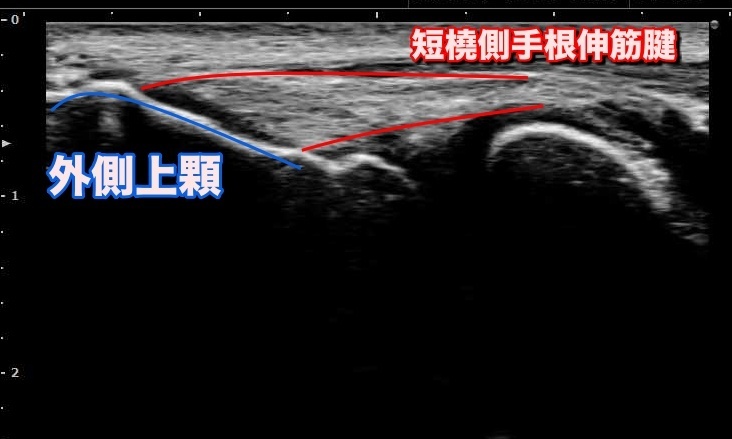

US(超音波検査)

検査査よる痛みが無く、被ばく等の身体に与える影響も無いため、小さなお子様や妊婦の方、ご高齢の方まで何度でも安心して検査をすることが出来ます。

レントゲン画像ではうつらない筋肉や腱、靭帯の損傷、内出血や軟骨、軟部腫瘍等の抽出に優れ、組織の炎症反応も確認出来ます。

簡便で安全に出来る反面、周辺を含めた全体像の把握や関節内や深層部の精査には不向きです。